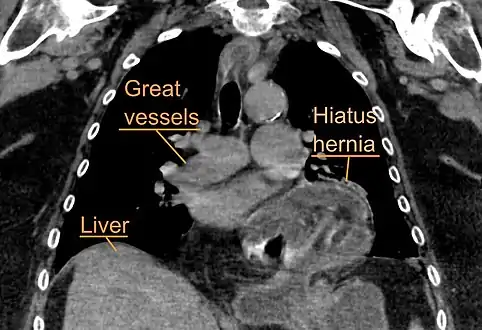

A large hiatal hernia as seen on CT imaging

A large hiatal hernia as seen on CT imaging- As seen on ultrasound[9]